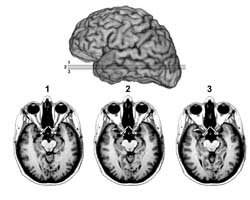

Em um raro caso, a paciente teve as chamadas amígdalas cerebrais destruídas por uma doença.

Essas estruturas em forma de amêndoa, uma de cada lado do cérebro, são conhecidas dos cientistas por estar associadas à geração de medo em animais, de ratos a macacos.